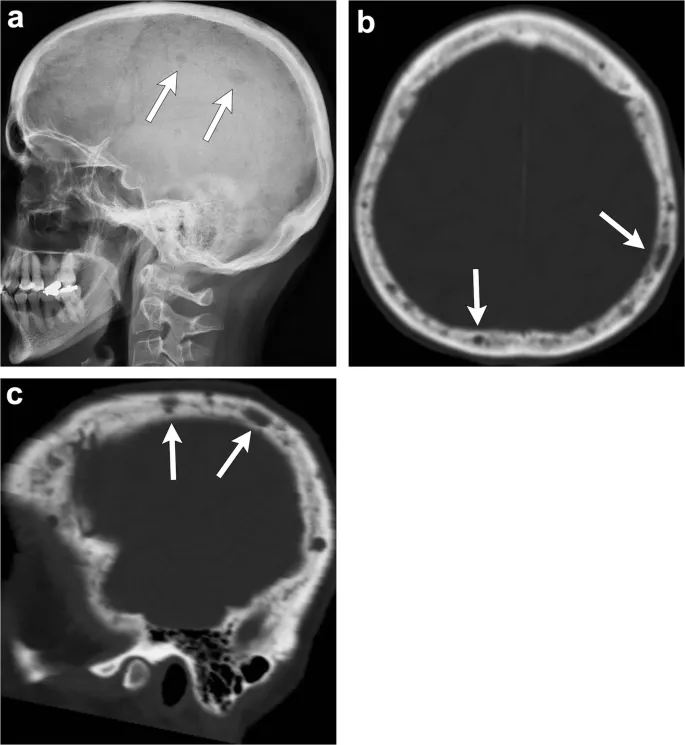

- 📌 CRAB Criteria: Calcium (>11.5 mg/dL), Renal insufficiency (Cr >2), Anemia (Hgb <10), Bone lytic lesions.